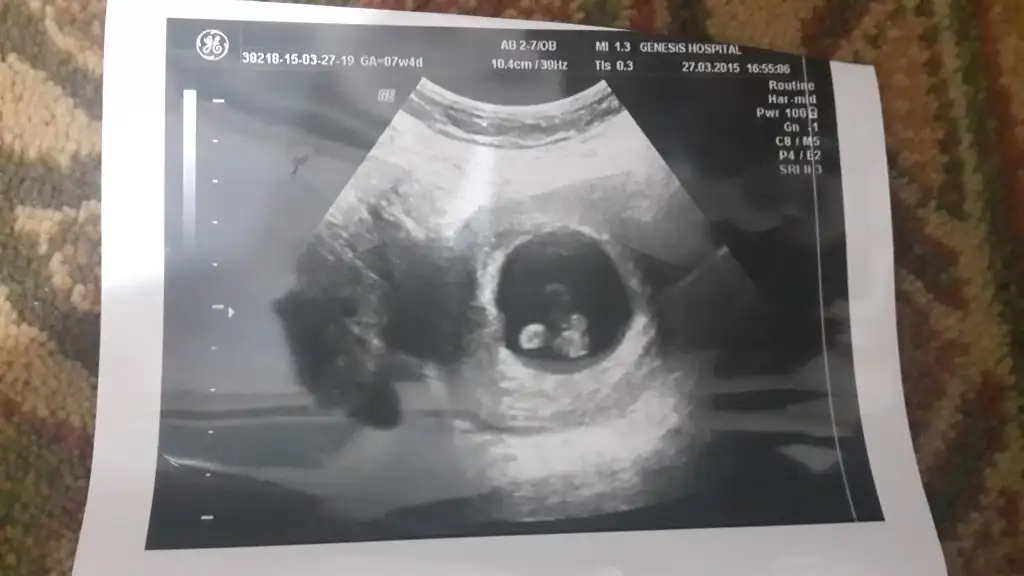

Bebegin Kesedeki Konumuna Göre Cinsiyet Tahmini

%100 doğruluk payı olmasa da insan merak ediyor :oops: Ben de kuzumun 9.haftalık görüntüsünü ekliyorum, yorum yaparsanız çok sevinirim:KK68: